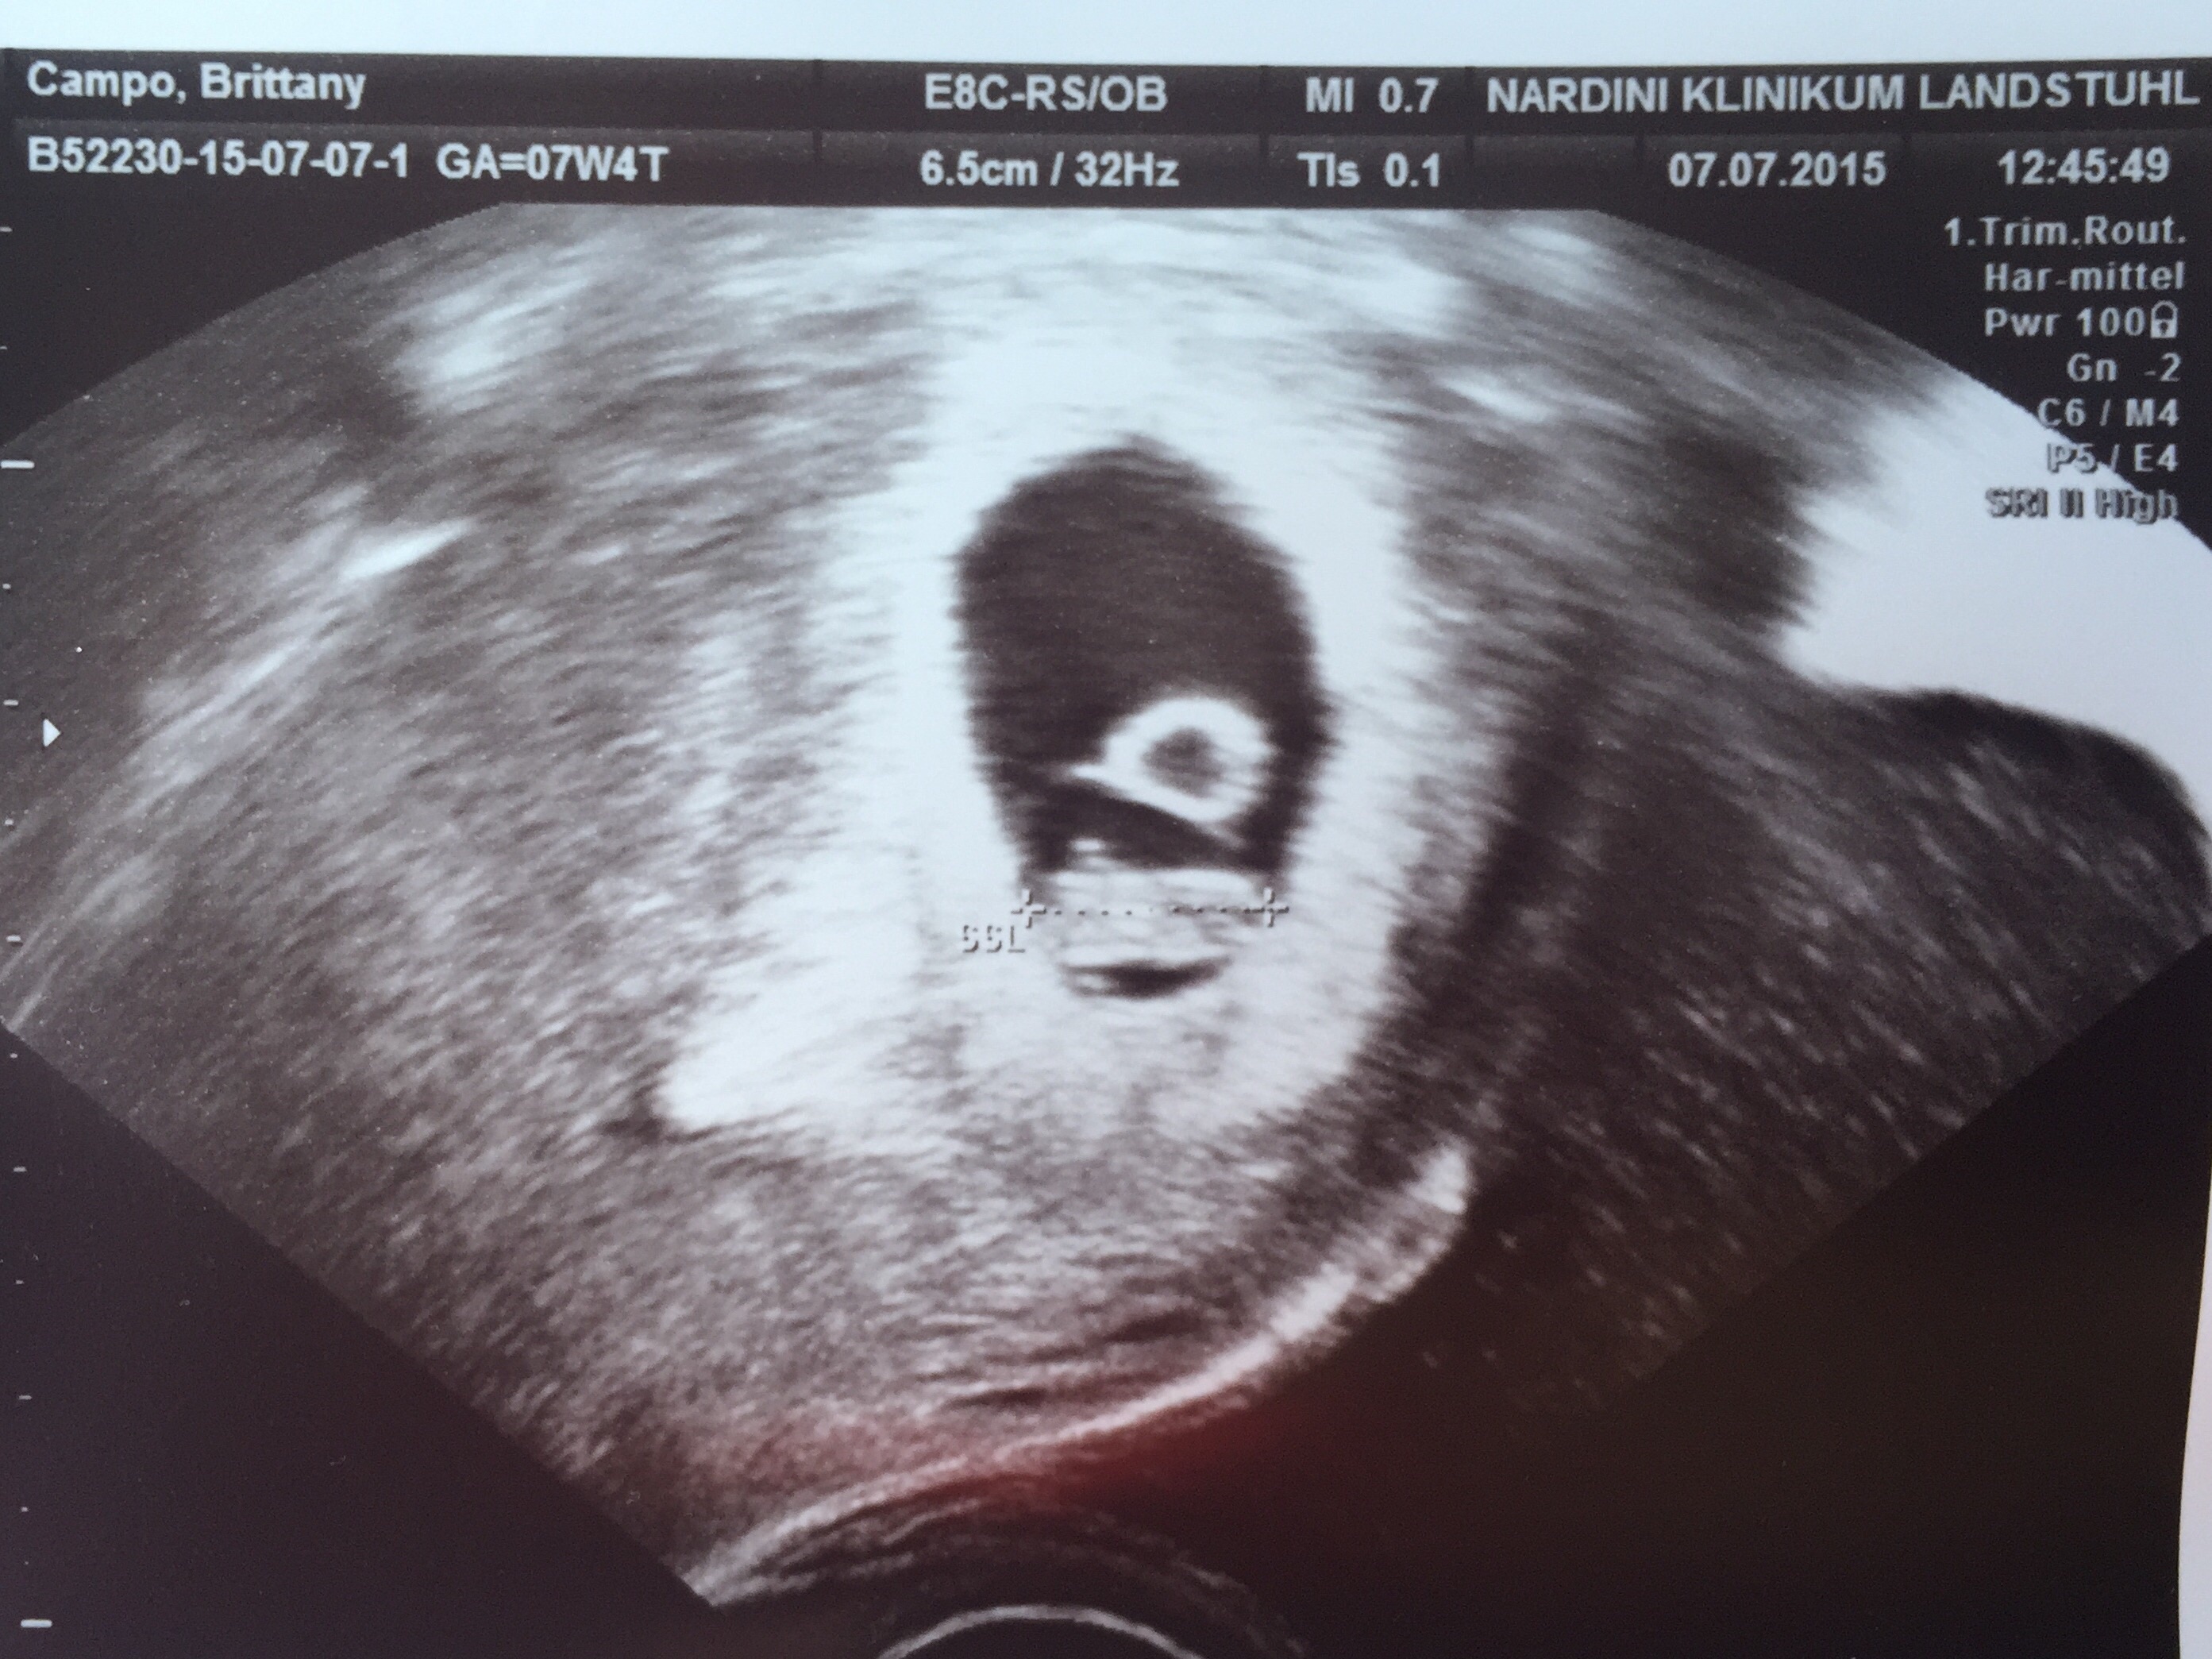

• So glad I get to finally post on this thread! First US today. I was really worries because my progesterone was low, but baby looks good :) heartbeat was 143. Not as far along as we originally thought, but not far behind. Right at 7 weeks. Due 2/23 :)